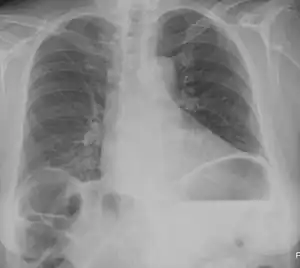

| Chest X-ray showing obvious Chilaiditi's sign, or presence of gas in the right colic angle between the liver and right hemidiaphragm. | |

Chilaiditi syndrome is a rare condition when pain occurs due to transposition of a loop of large intestine (usually transverse colon) in between the diaphragm and the liver, visible on plain abdominal X-ray or chest X-ray.[1]

Normally this causes no symptoms, and this is called Chilaiditi's sign. The sign can be permanently present, or sporadically. This anatomical variant is sometimes mistaken for the more serious condition of having air under the diaphragm (pneumoperitoneum) which is usually an indication of bowel perforation, possibly leading to surgical interventions.